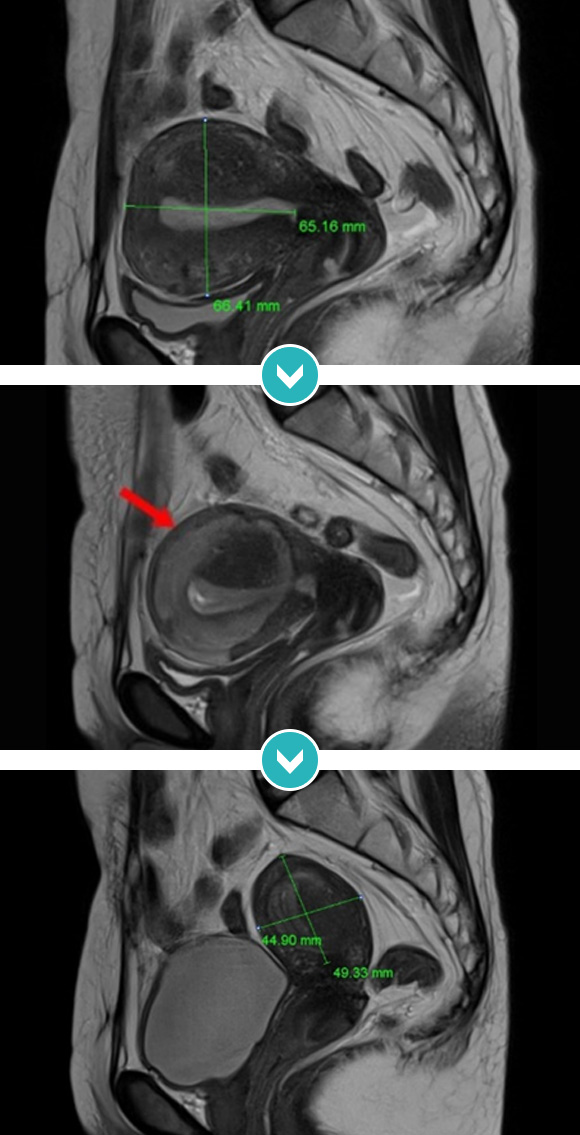

6cm 크기 자궁후벽의 자궁선근증 하이푸 치료후 80~90%이상 치료, 6개월 추적관찰